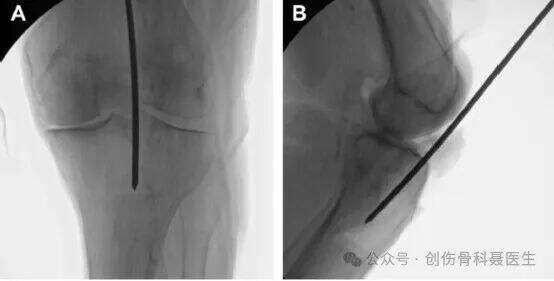

Insision & införingspunkt:

AP-visning: Inträdespunkten ligger vid skärningspunkten mellan tibians mekaniska axel och tibialplattan. Detta motsvarar en punkt precis medialt om den laterala interkondylära utväxten. Rita en linje parallell med den mekaniska axeln på en standard AP-radiografi, placerad på den laterala sidan av tibialplattan; denna linje bör dela fibulahuvudet mitt itu.

Sidovisning: På en standard lateral radiografi (där femoralkondylerna och tibialplattorna överlappar varandra) ligger införingspunkten vid "vatten-skiljelinjen" – samsättningen (övergångszonen) mellan den anterioara randen av tibialplattan och början av tibiaskaftet.